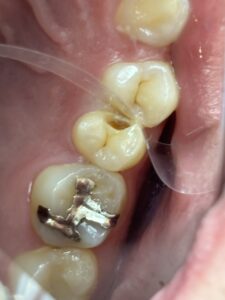

虫歯で奥歯が欠けてズキズキ痛い、噛めない 咬みにくい 食事もだんだんしづらく ついでに歯が冷たい水にしみる!

歯の神経を取る根の治療 根管治療をすれば治ります。治した後は 保険適応でハイブリッドセラミックやCAD/CAM冠インレー クラウンなどで白い歯で治すといいですね。もちろんセラミックやジルコニアの治療もあります。